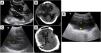

More infoAn 18-year-old male with a history of severe traumatic brain injury developed severe hydrocephalus (Fig. 1, asterisks) after bilateral decompressive craniectomy, as shown by transcranial ultrasound (TCU, Fig. 1A) and cranial computed tomography (CT, Fig. 1B). Subsequently, the patient underwent a one-stage bilateral cranioplasty and ventriculoperitoneal (VP) shunt placement. Postoperatively, a progressive reduction in lateral ventricle size was observed on serial TCU (Fig. 1C) and CT as well (Fig. 1D). Notably, on abdominal ultrasound, the VP shunt catheter tip (Fig. 1E, arrow) was observed within the free peritoneal fluid (Fig. 1E, X-sign), indicating cerebrospinal fluid drainage. Ongoing monitoring of hydrocephalus and VP shunt function is an emerging application of point-of-care ultrasound that may aid in the early detection of system malfunction and expediting therapeutic interventions.